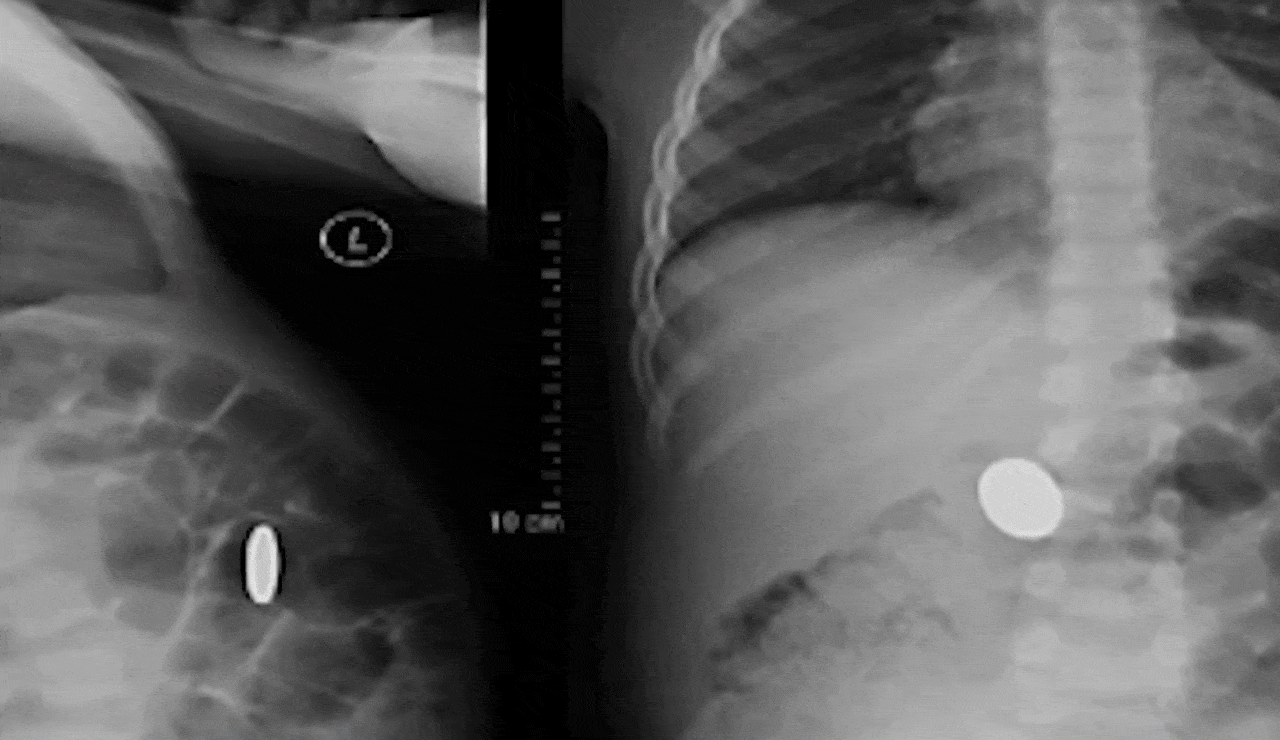

According to doctors at JN Medical College, the woman underwent an X-ray of the abdomen after experiencing unusual symptoms during her work. The X-ray revealed that a coin, which she had accidentally swallowed as a child, had been lodged in her stomach all these years.

The coin was successfully removed through an endoscopy, a procedure that uses a flexible tube with a camera to examine and treat internal parts of the body. The woman’s medical condition was attributed to the coin’s magnetic effect, which caused strange movements and severe pain in her stomach while she was operating MRI equipment on patients.